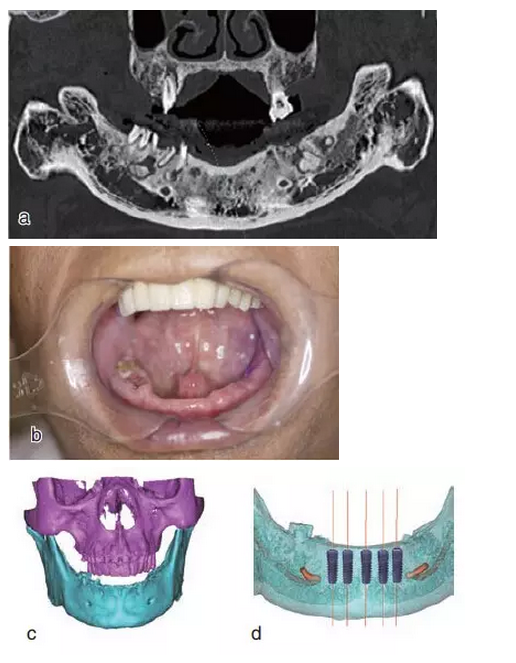

設(shè)計(jì)切口,剝離黏骨膜后,將截骨導(dǎo)板戴到骨面上,用咬骨鉗沿著截骨導(dǎo)板平面進(jìn)行截骨,并用骨銼修整骨平面,截骨完成后將種植導(dǎo)板固定在骨面上進(jìn)行種植備孔,完成后植入種植體。注意截骨平面要平整,否則影響種植導(dǎo)板的就位。

戴上套筒冠基臺(tái)進(jìn)行即刻修復(fù)。注意不是所有植入的種植體都可以進(jìn)行即刻修復(fù),醫(yī)師可以通過(guò)扭力值并結(jié)合ISQ松動(dòng)度測(cè)量值來(lái)選擇修復(fù)的種植體。

圖18

進(jìn)行即刻修復(fù):a.戴上基臺(tái);b.在基臺(tái)上戴入套筒冠;c. 套筒冠固位到原有義齒上;d.患者戴上有套筒冠的覆蓋義齒;e.

即刻修復(fù)完成后曲面體層片